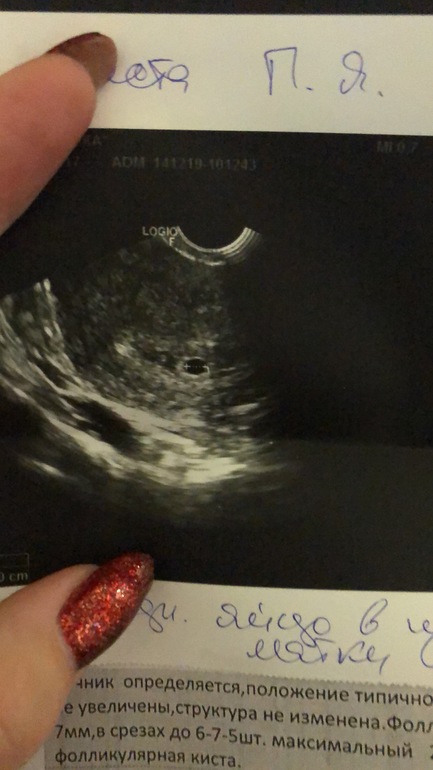

УЗИ, КТГ, доплерАкушерских срок 4 недели и 3 дня.

Визуализируется ПЯ 0,5 см.)

Но, есть фолликулярная киста, 3 см. Первый раз с таким столкнулась. Это опасно? Кто нибудь знает?

А это мой пупсик ))